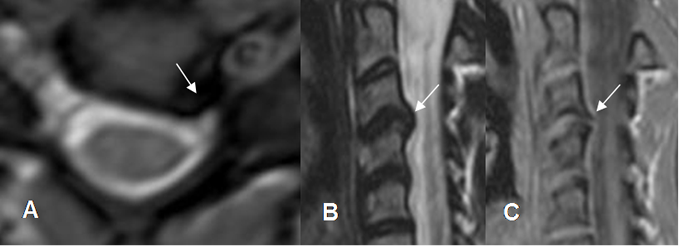

Fig 93. Hernia de disco.

A: RM sagital en T2 y B: RM sagital en GE. Protrusiones del disco, que indentan el saco dural. (Flechas gruesas). Adicionalmente se aprecian osteofitos anteriores y posteriores. (Flechas delgadas).

Fig 94. Osteofito cervical.

A: RM axial y B: RM sagital en T2. Ocupación del receso lateral izquierdo, por imagen hipointensa que desplaza la raíz.

C: RM sagital en GE. La compresión es ocasionada por osteofito, pudiendo identificar su cortical.